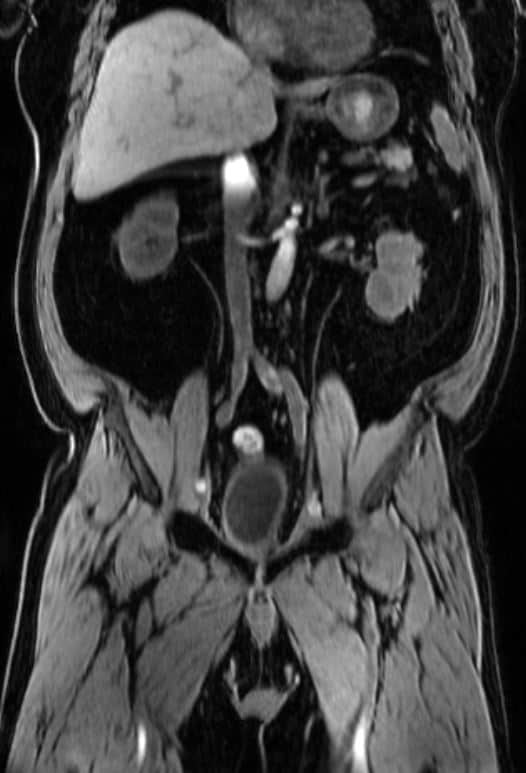

Eksempler på MR-scanninger

Maveregionen (abdomen) indeholder livsvigtige organer, der varetager kroppens fordøjelse, stofskifte og udskillelse af affaldsstoffer. Disse organer inkluderer lever, galdeblære, bugspytkirtel, milt, nyrer, binyrer, tarmene og for kvinder også de indre kønsorganer. På grund af mavens komplekse sammensætning af organer er præcis diagnosticering afgørende for effektiv behandling.

En MR-scanning af maven er en avanceret, non-invasiv billeddiagnostisk metode, der skaber ekstremt detaljerede billeder af alle maveregionens bløddelsorganer. Ved hjælp af kraftige magnetfelter og radiobølger kan vi visualisere:

- Lever og dens indre struktur

- Galdeblære og galdegange (MRCP)

- Bugspytkirtel (pancreas)

- Milt

- Nyrer og binyrer

- Blære

- Tarmkanalen

- Blodkar og lymfeknuder

- Muskler og omgivende væv

- Hovedpulsåren (aorta)